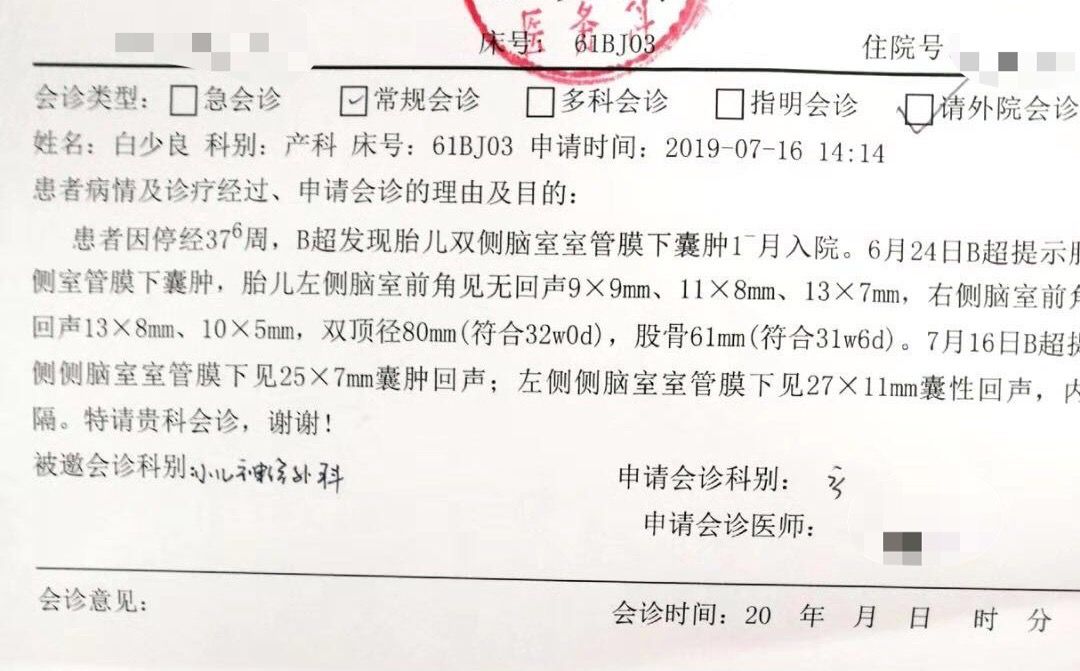

会诊记录